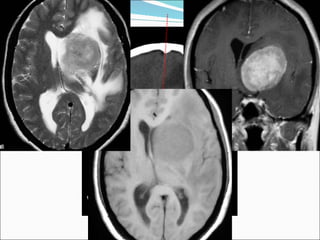

Radiology:  Glioblastoma is usually seen as a  grossly heterogeneous mass . R ing enhancement surrounding a necrotic center  is the most common presentation, but there may be multiple rings. Characterized by  irregular ring-enhancement surrounding a central non-enhancing region of necrosis . Note the shaggy inner-margin of the ring, and the remarkable variation in its thickness. The small foci of internal enhancement represent islands of  living tumor within the regions of necrosis .  Surrounding vasogenic edema  can be impressive, and adds significantly to the mass effect.  Glioblastoma multiforme ( GBM) Axial Gd Enhanced T1W MRI Axial T2W MRI

Radiology: Glioblastomais usually seen as a grossly heterogeneous mass . R ing enhancement surrounding a necrotic center is the most common presentation, but there may be multiple rings. Characterized by irregular ring-enhancement surrounding a central non-enhancing region of necrosis . Note the shaggy inner-margin of the ring, and the remarkable variation in its thickness. The small foci of internal enhancement represent islands of living tumor within the regions of necrosis . Surrounding vasogenic edema can be impressive, and adds significantly to the mass effect. Glioblastoma multiforme ( GBM) Axial Gd Enhanced T1W MRI Axial T2W MRI

• #34 WHO Grade IV Cell of Origin: ASTROCYTE Synonyms: GBM, glioblastoma multiforme, spongioblastoma multiforme Common Locations: cerebral hemispheres, occasionally elsewhere (brainstem, cerebellum, cord) Demographics: peak from 45-60 years Histology: grossly heterogeneous, degeneration, necrosis and hemorrhage are common Special Stains: GFAP varies, often present in areas of better differentiation Progression : Can't get any worse. Radiology: Glioblastoma is usually seen as a grossly heterogeneous mass. Ring enhancement surrounding a necrotic center is the most common presentation, but there may be multiple rings. Surrounding vasogenic edema can be impressive, and adds significantly to the mass effect. Signs of recent (methemoglobin) and remote (hemosiderin) hemorrhage are common. Despite it’s apparent demarcation on enhanced scans, the lesion may diffusely infiltrate into the brain, crossing the corpus callosum in 50-75% of cases.